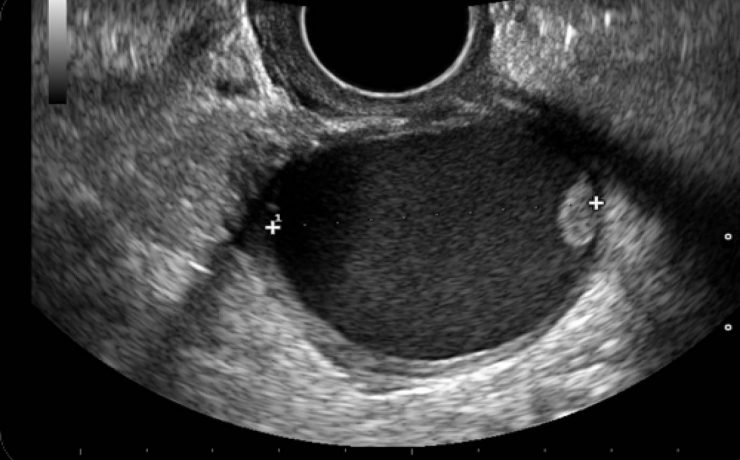

Correlación ultrasonográfica e histopatológica de los tumores de ovario

El cáncer de ovario, constituye el 2 % de las afecciones malignas de la mujer con una alta mortalidad, aproximadamente las dos terceras partes se presentan con lesiones muy avanzadas en el momento del examen imagenológico,1-4 trae por consecuencia una supervivencia menor de la paciente y un aumento del costo